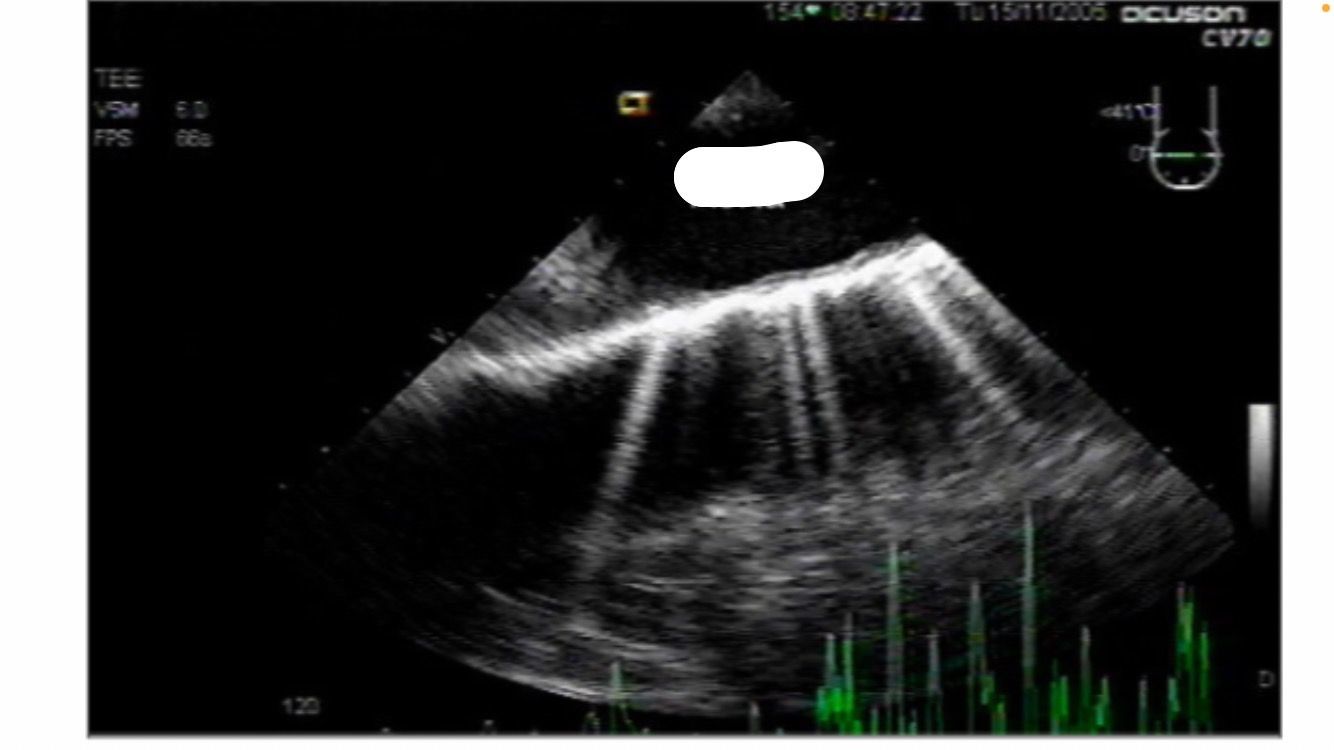

Midesophageal ascending aortic short axis SAX

descending aortic LAX